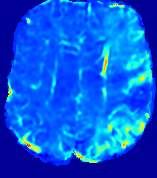

LesionRefer to captionRefer to captionRefer to captionRefer to captionRefer to captionRefer to caption𝐕rgbsubscript𝐕𝑟𝑔𝑏{\bf{V}}_{rgb}Refer to captionRefer to captionRefer to captionRefer to captionRefer to captionRefer to caption𝐕2subscriptnorm𝐕2{\|\bf{V}}\|_{2}Refer to captionRefer to captionRefer to captionRefer to captionRefer to captionRefer to captionRefer to caption3.53.53.52.82.82.82.12.12.11.41.41.40.70.70.70.00.00.0(mm/s)𝑚𝑚𝑠(mm/s)D𝐷DRefer to captionRefer to captionRefer to captionRefer to captionRefer to captionRefer to captionRefer to caption0.0200.0200.0200.0160.0160.0160.0120.0120.0120.0080.0080.0080.0040.0040.0040.0000.0000.000(mm2/s)𝑚superscript𝑚2𝑠(mm^{2}/s)Slice #1Slice #2Slice #3Slice #4Slice #5Slice #6

Figure 4: PIANO feature maps for another patient in the ISLES 2017 training set, where the lesion is located in the right hemisphere. Top row: segmented stroke lesion region (white) on different slices. The corresponding slices for the PIANO feature maps are shown in the following rows.

For a better insight into an estimated velocity field 𝐕𝐕{\bf{V}} and diffusion field 𝐃𝐃{\bf{D}}, we compute the following maps: (1) 𝐕rgbsubscript𝐕𝑟𝑔𝑏{\bf{V}}_{rgb}: Color-coded orientation map of 𝐕=(Vx,Vy,Vz)T𝐕superscriptsuperscript𝑉𝑥superscript𝑉𝑦superscript𝑉𝑧𝑇{\bf{V}}=(V^{x},V^{y},V^{z})^{T}, obtained by normalizing 𝐕𝐕{\bf{V}} to unit length and mapping its 3 components to red, green, blue respectively; (2) 𝐕2subscriptnorm𝐕2\|{\bf{V}}\|_{2}: 222 norm of 𝐕𝐕{\bf{V}}; (3) D𝐷D: scalar field in Eq. 5.

Fig. 3 and Fig. 4 show the PIANO feature maps estimated from two ISLES 2017 patients: all are highly consistent with the lesion in both cases. Details of the blood flow trajectories are revealed in 𝐕rgbsubscript𝐕𝑟𝑔𝑏{\bf{V}}_{rgb} by the ridged patterns and the sharp changes of colors in the unaffected (right) hemisphere, while the flat patterns appearing within the lesion provide little directional information about the velocity and indicate low velocity magnitudes. Velocity magnitudes are more directly visualized via 𝐕2subscriptnorm𝐕2\|{\bf{V}}\|_{2}, from which one can easily locate the lesion where 𝐕2subscriptnorm𝐕2\|{\bf{V}}\|_{2} is low. D𝐷D also indicates lower diffusion values in the lesion, though with less contrast potentially due to the fact that it captures the accumulated effect of CA diffusion at the voxel-level.